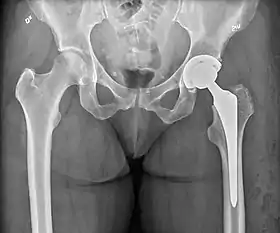

Post-operative projectional radiography is routinely performed to ensure proper configuration of hip prostheses.

The direction of the acetabular cup influences the range of motion of the leg, and also affects the risk of dislocation.[7] For this purpose, the acetabular inclination and the acetabular anteversion are measurements of cup angulation in the coronal plane and the sagittal plane, respectively.

Center of rotation: The horizontal center of rotation is calculated as the distance between the acetabular teardrop and the center of the head (or caput) of the prosthesis and/or the native femoral head on the contralateral side.[69] The vertical center of rotation instead uses the transischial line for reference.[69] The parameter should be equal on both sides.[69]